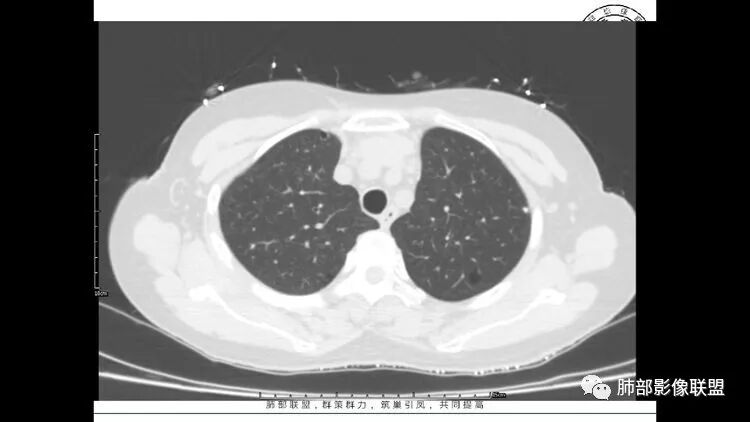

老年女性,眼炎入院,血常规正常,双肺多发囊状影,病变随机分布,形态单一,与血管关系密切,考虑LIP。左下肺混合GGO,边界尚清,贴近囊腔,鉴别腺癌。炎症指标无异常暂不考虑感染性病变。

胸CT:1.双肺多发囊性变,以中下肺为主,病变边缘可见肺动脉,部分囊内可见分隔及肺动脉,双下部分肺野周围可见小叶中心结节及树丫征。

2 左肺上叶尖后段 右肺上叶前段 右肺下叶外基底段 结节影,边界清楚,可见柔软毛刺,左肺下叶后基底段混合密度影。

3.纵隔淋巴结肿大?,以主动脉弓为界向上向下增大。

考虑:淋巴瘤肺浸润,眼部症状考虑与此有关;LIP?;继续鉴别肺腺癌?血管炎?。